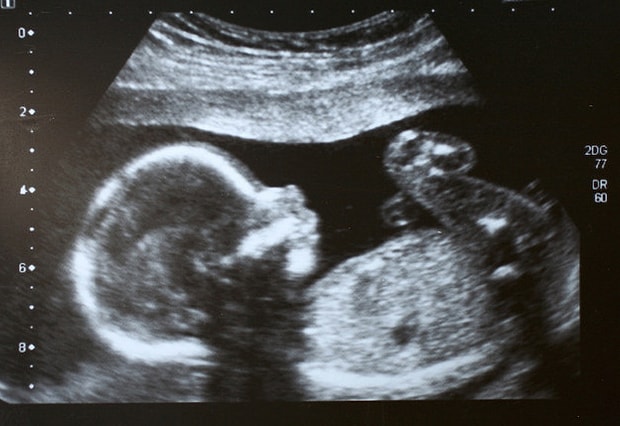

Bebek eğer anne karnının sağ tarafında hareket ediyor ise erkek bebek olacağına inanılır. Erkek Bebek Kesesi Hangi Tarafta Olur. Gebelikte erkek bebeğin hareketleri genellikle karnın sağ tarafında olur. Aşermeler hamilelik sırasında oldukça doğal durumlardır. Anne karnında bebek sağ tarafta olursa cinsiyeti ne olur sorularının cevabını arıyor.

Erkek ise yatak. Bebek eğer anne karnının sağ tarafında hareket ediyor ise erkek bebek olacağına inanılır. Erkek bebek nasıl belli olur diye merak edenlere verilebilecek cevaplar aşağıdaki şekilde sıralanabilir. Hamileyken bebeğin sağ tarafta olmasını sağ memenin daha büyük olması ayak üşümesi ve bulantı azlığı takip edebilir. Plasenta eğer sağ tarafta görülüyor ise bu X ve Y kromozomlarına işaret.

Aşerilen gıdalar kişiden kişiye değişiklik gösterir. Fakat erkek bebek taşıyor iseniz sağ meme diğer memeden daha büyük bir görüntüye sahip olabilir. Hamileyken bebeğin sağ tarafta olmasını sağ memenin daha büyük olması ayak üşümesi ve bulantı azlığı takip edebilir. Anne karnında bebek sağ tarafta olursa cinsiyeti ne olur sorularının cevabını arıyor. Bebek eğer anne karnının sağ tarafında hareket ediyor ise erkek bebek olacağına inanılır.